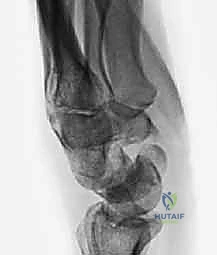

- الأشعة السينية الرقمية (Digital X-rays): بأوضاع متعددة (AP, Lateral, Scaphoid view) لتقييم زوايا العظام ودرجة الانهيار.

- الأشعة المقطعية (CT Scan): وهي المعيار الذهبي لتقييم حجم العظم المتآكل بدقة ثلاثية الأبعاد، وتحديد مدى الخشونة في المفاصل المحيطة.

- الاستئصال الدقيق: باستخدام أدوات جراحية ميكروسكوبية دقيقة، يتم استئصال حوالي 3 إلى 4 مليمترات من القطب البعيد للعظم الزورقي. هذه الكمية كافية لمنع الاحتكاك مع عظم الكعبرة، وفي نفس الوقت تحافظ على استقرار الأربطة.